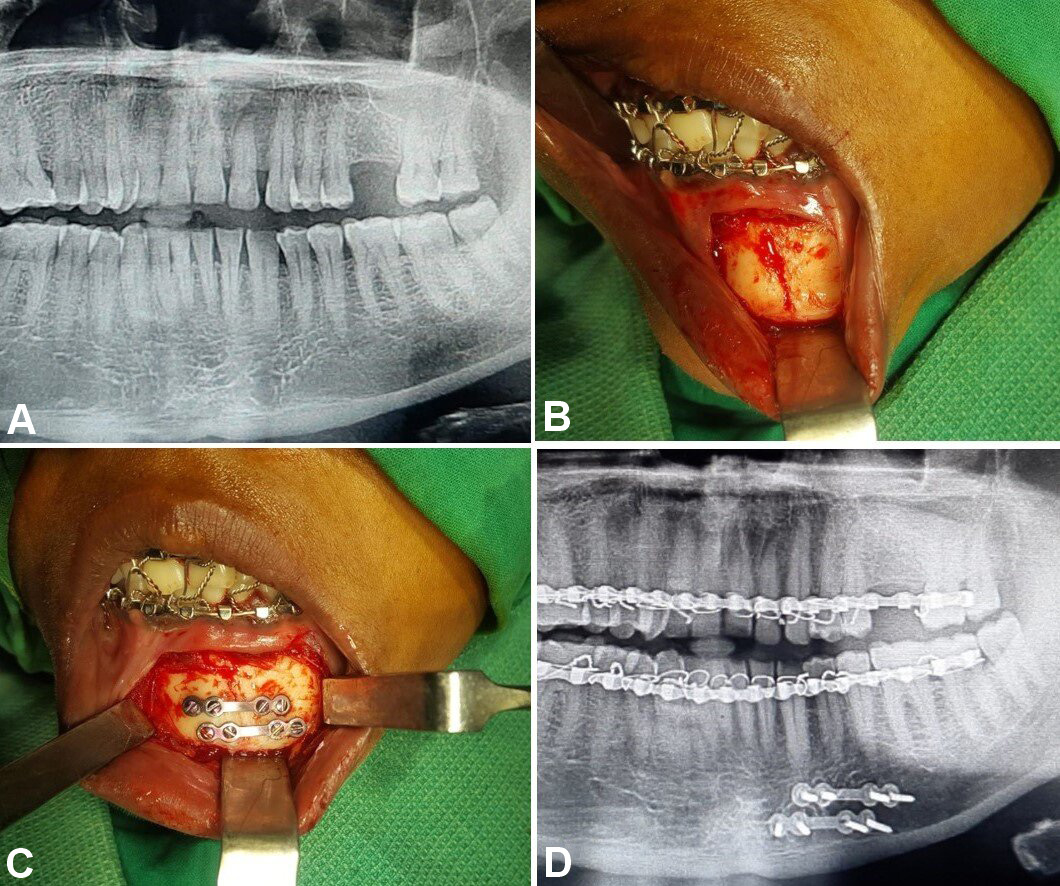

In group A, fixation was performed using 2 titanium microplates (0.8-mm, 4-hole design with a gap) and 8 microscrews (1.5 mm × 8 mm and 1.5 mm × 10 mm), which were placed subapically and at the inferior border of the mandible according to Champy’s lines of osteosynthesis (Figure 2, Figure 3, Figure 4).